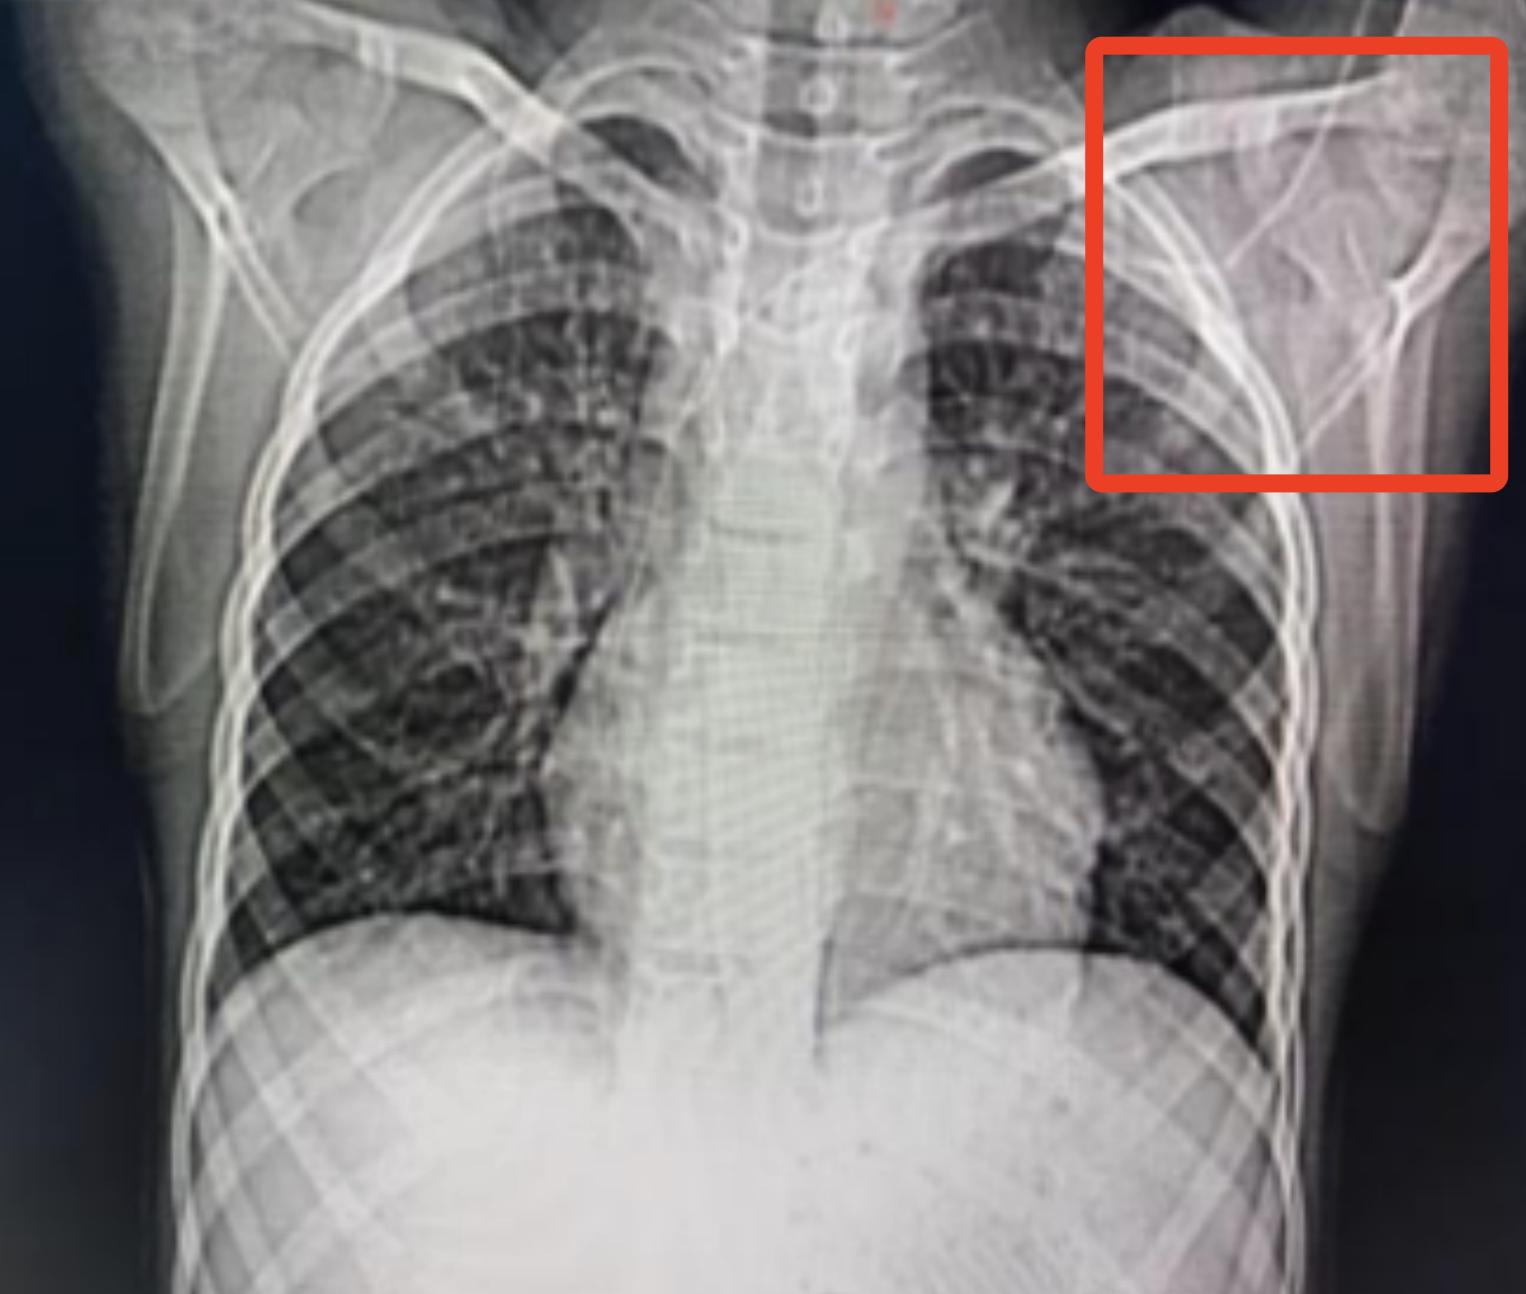

孩子全麻下行经皮血管内异物取出术,术前CT及胸片显示腋静脉段导管弯折断裂,随后复查CT及三维重建显示:导管断裂,远端漂移至右下肺动脉。

术中发现断裂的PICC导管漂浮至右侧肺下动脉远端,一端飘浮在肺动脉干,采用经皮血管内利用抓捕器抓捕住导管近端,轻柔拖拽导管,将断裂导管取出。